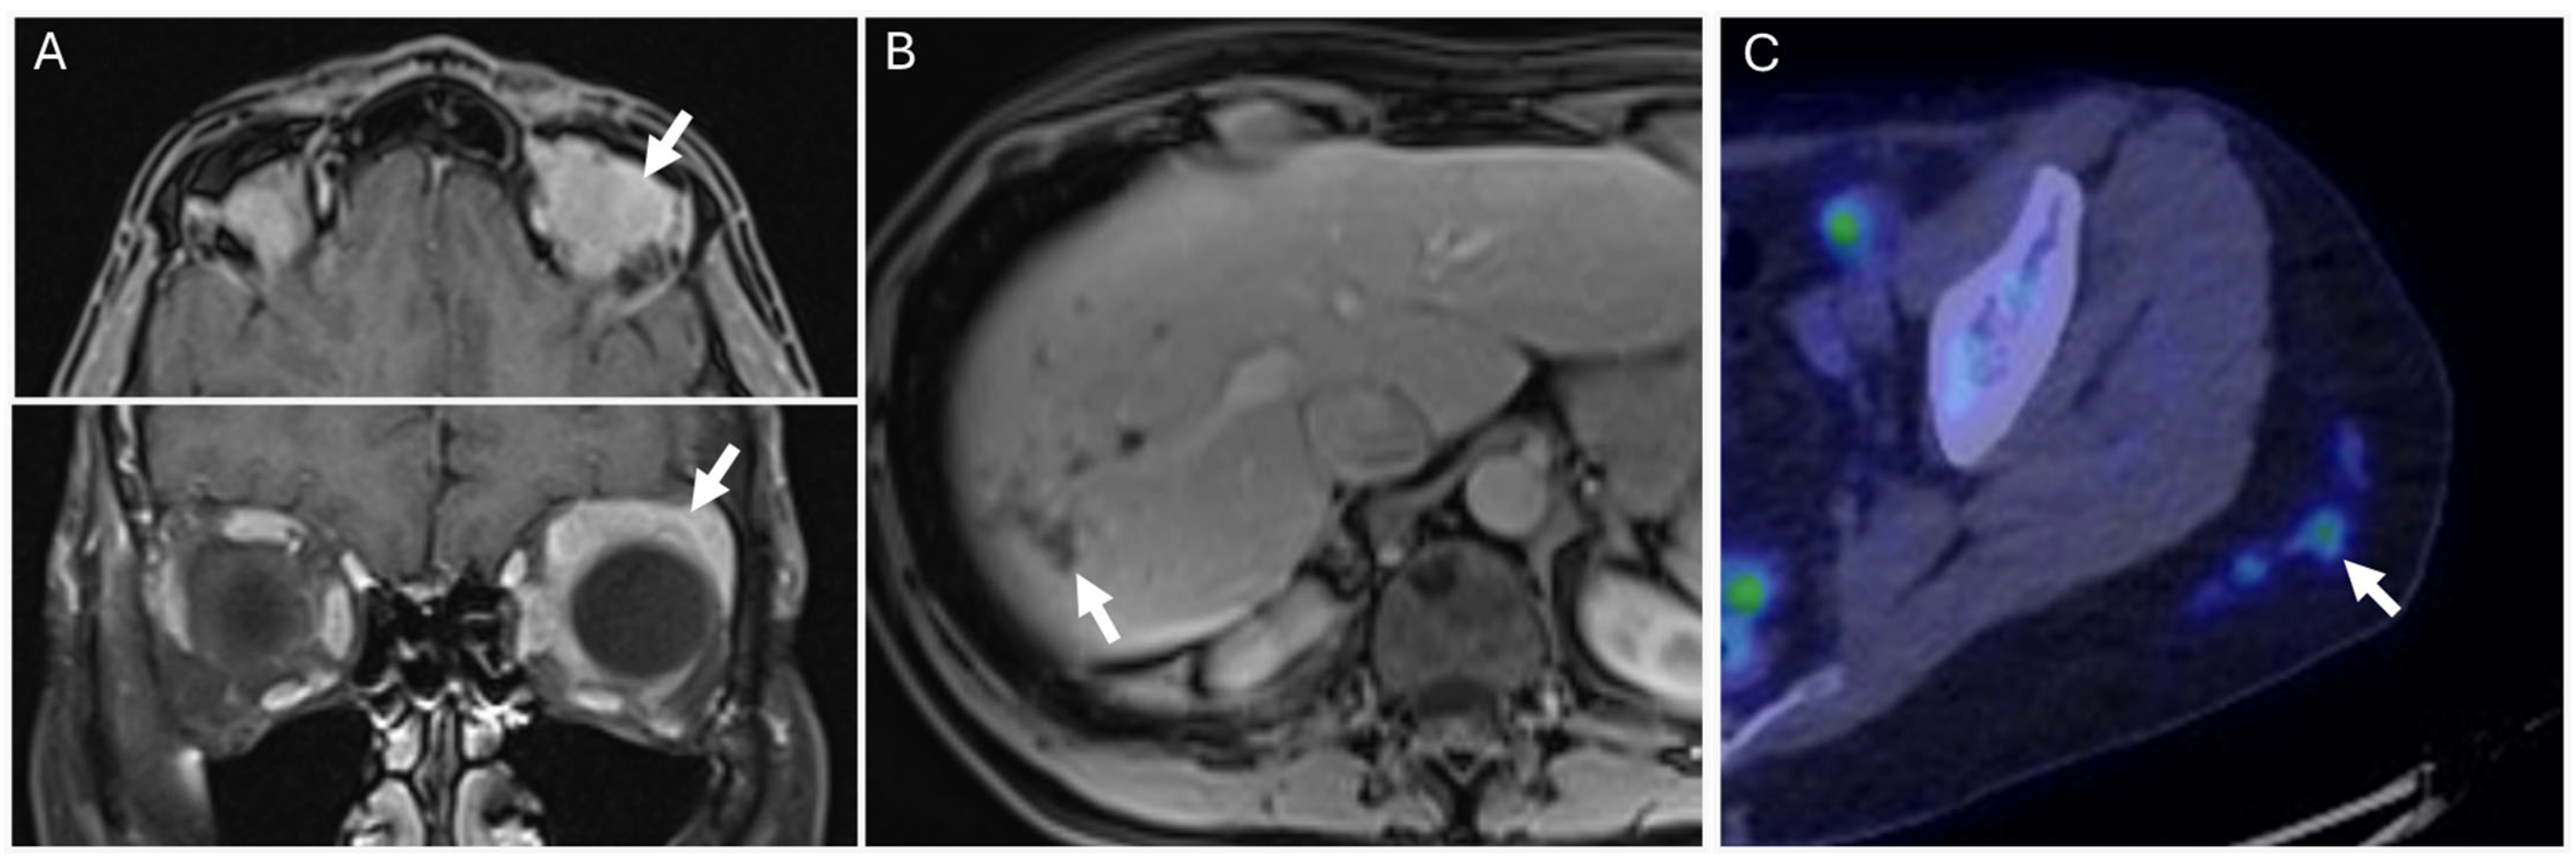

3.1. POEMS Syndrome